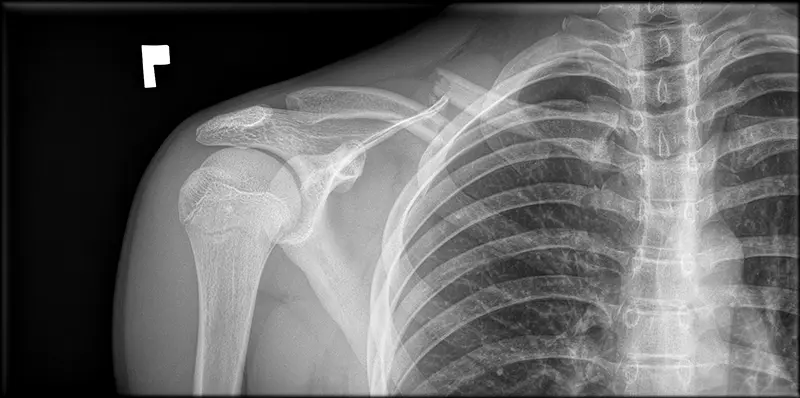

Wskazania do operacji zależą od rodzaju złamania, przemieszczenia fragmentów, obecności uszkodzeń towarzyszących oraz indywidualnych okoliczności pacjenta. W niektórych przypadkach, zwłaszcza gdy złamanie jest przesunięte i nie może być poprawione za pomocą leczenia zachowawczego, konieczna jest interwencja chirurgiczna. Operacja może obejmować umieszczenie płytki i śrub w celu stabilizacji złamanego obojczyka.